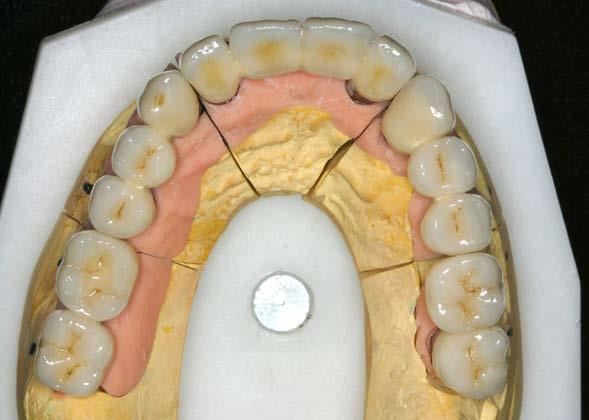

Figura 4. Prótesis de carga progresiva finalizada, lista para su colocación.

5 y 6. Prótesis atornillada de carga progresiva en la fase previa a la confección de la prótesis definitiva.

En el arco superior se planifica una rehabilitación cementada por tramos, que en ese contexto representaba la mejor alternativa en términos de estética y estanqueidad, mediante pilares específicos para fresado. Para ello se programan 10 implantes. En una primera fase se realiza la carga inmediata

del sector anterior y la carga definitiva de los implantes mandibulares mediante una prótesis de resina atornillada (Figura 3).

Seis meses después se cargan los implantes de los sectores posteriores con una prótesis atornillada sobre transepiteliales de larga duración en metal-resina, lo que permite generar una carga controlada y favorecer la adecuada conformación de los tejidos periimplantarios (Figura 4).

Una vez alcanzada la estabilidad de los tejidos blandos, 6 meses después de la carga progresiva se inicia la confección de la prótesis definitiva (Figuras 5 y 6).

El diseño de la prótesis superior se basa en la confección de pilares de oro ceramizado en los sectores anteriores, con el objetivo de optimizar la estética, y biopilares fresables en la zona posterior. Estos pilares permiten una correcta adaptación al perfil gingival y presentan un adecuado grado de estanqueidad, minimizando el riesgo de microfiltraciones que puedan favorecer infecciones periimplantarias. Hace 25 años constituían una de las mejores alternativas estéticas y funcionales para este tipo de rehabilitaciones.